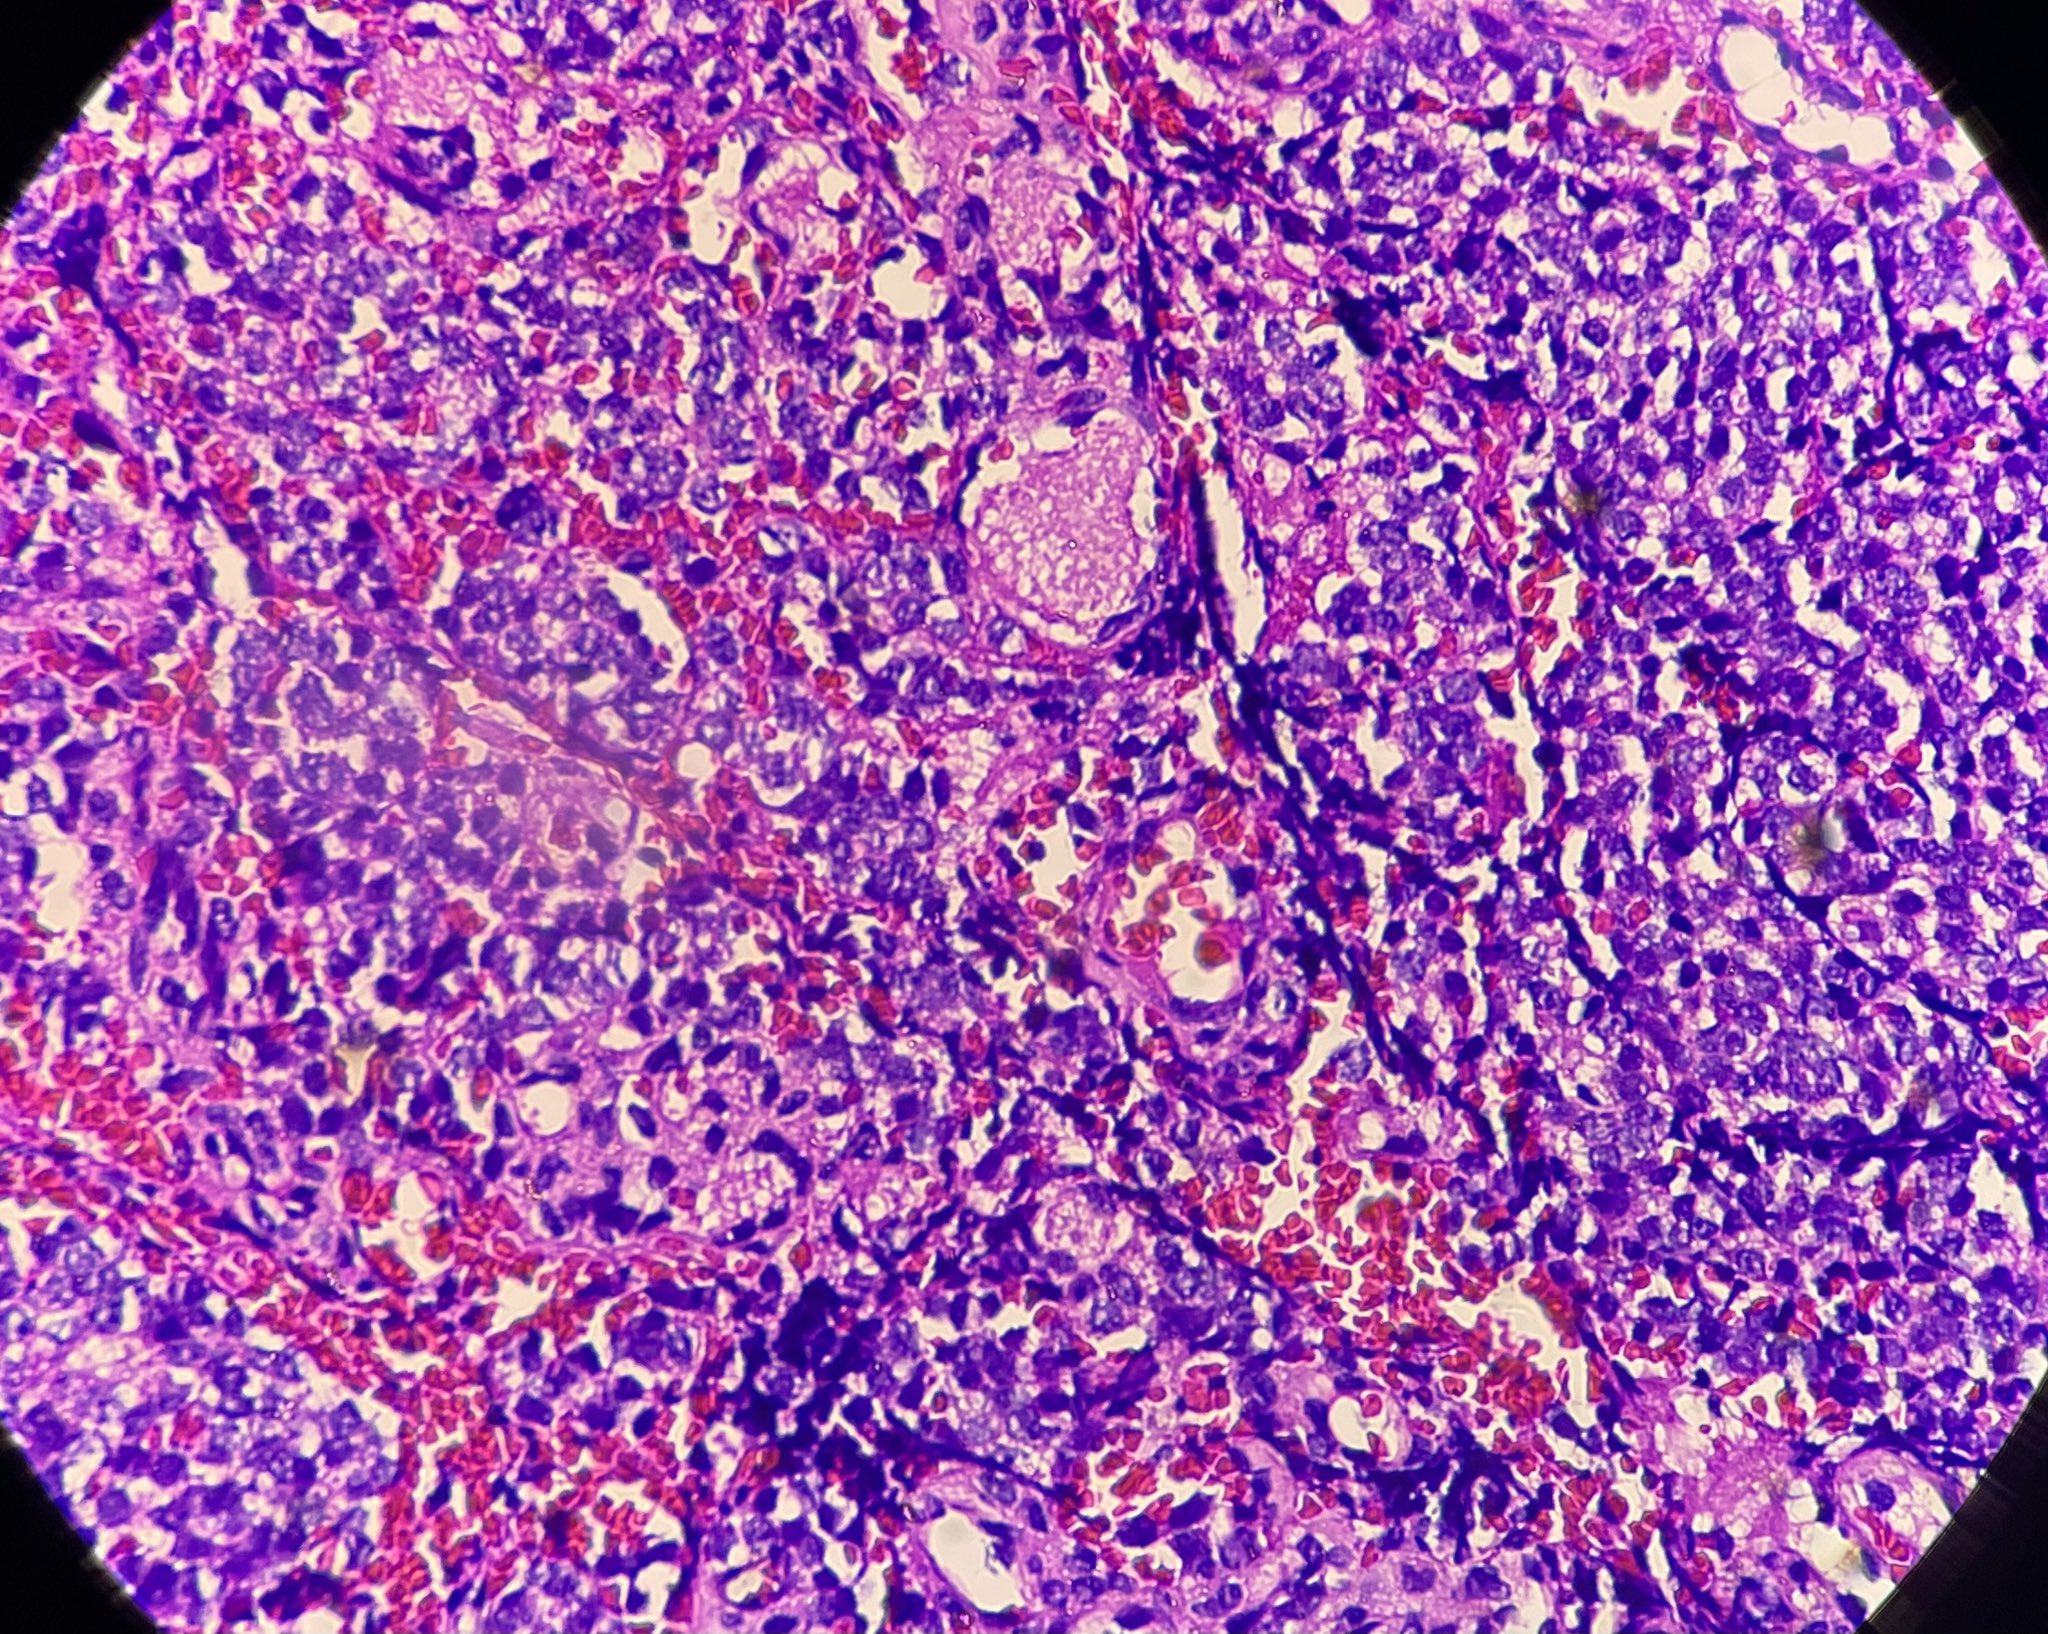

Suu @suulynnz · 5d 34 yr old, ethmoidal sinus tumour Endoscopy finding- highly vascular friable tumour Your opinion plz #pathX #pathtwitter #ENTPath #H&N 4 4 29 2.1K